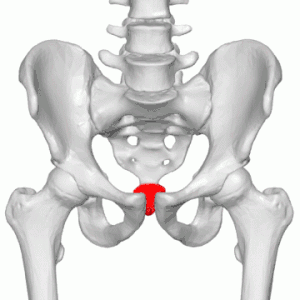

Coccyx fracture

A coccyx fracture is a break in the coccyx, and typically presents with 'tail bone' pain after a fall backwards onto the bottom.[1] The pain tends to worsen on sitting for long periods of time or when getting up from sitting.[1]